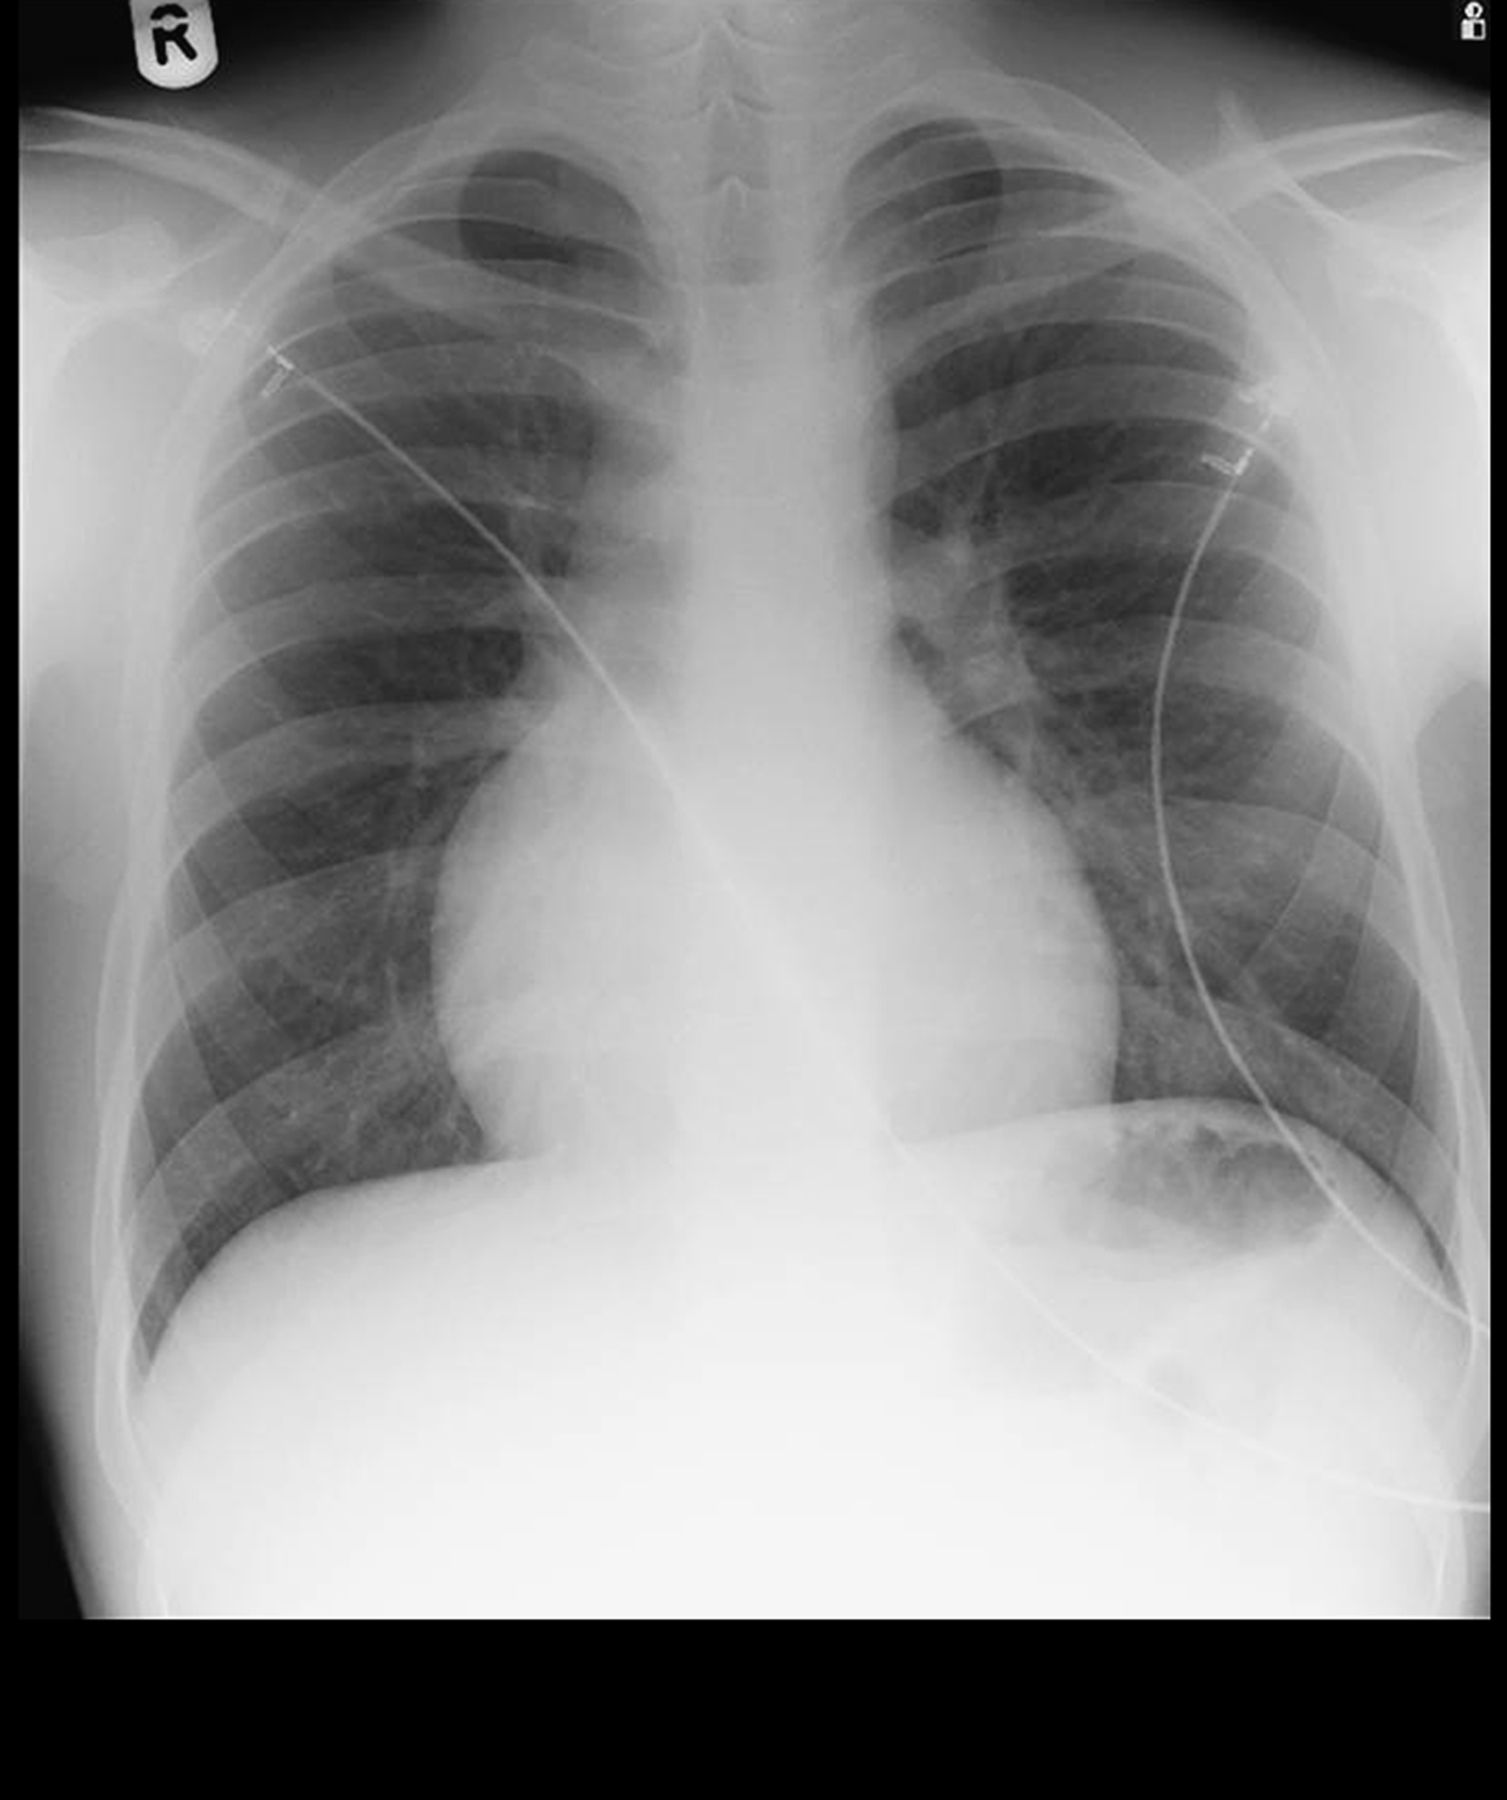

Left Ventricle Enlarged

Heart Enlarged